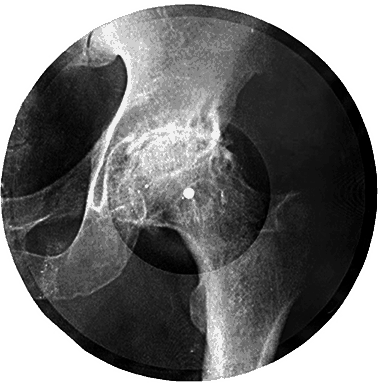

Диск «на костях»

Спрос на поп-записи в конце 50‑х – начале 60‑х был уже очень велик, а пластинок и магнитофонов катастрофически не хватало. Это вызвало к жизни легендарный феномен – достопамятные диски «на ребрах». Я видел несколько архивных экземпляров. Это настоящие рентгеновские снимки – грудная клетка, позвоночник, переломы костей – с маленькой круглой дыркой посередине, слегка закругленными ножницами краями и еле заметными звуковыми бороздками. Столь экстравагантный выбор исходного материала для «гибких грампластинок» объясняется просто: рентгенограммы были самыми дешевыми доступными носителями. Их скупали сотнями за копейки в поликлиниках и больницах, после чего с помощью специальных машин – говорят, законспирированные умельцы переделывали их из старых патефонов – нарезали дорожки, копируя пластинку-оригинал или магнитофонную запись.